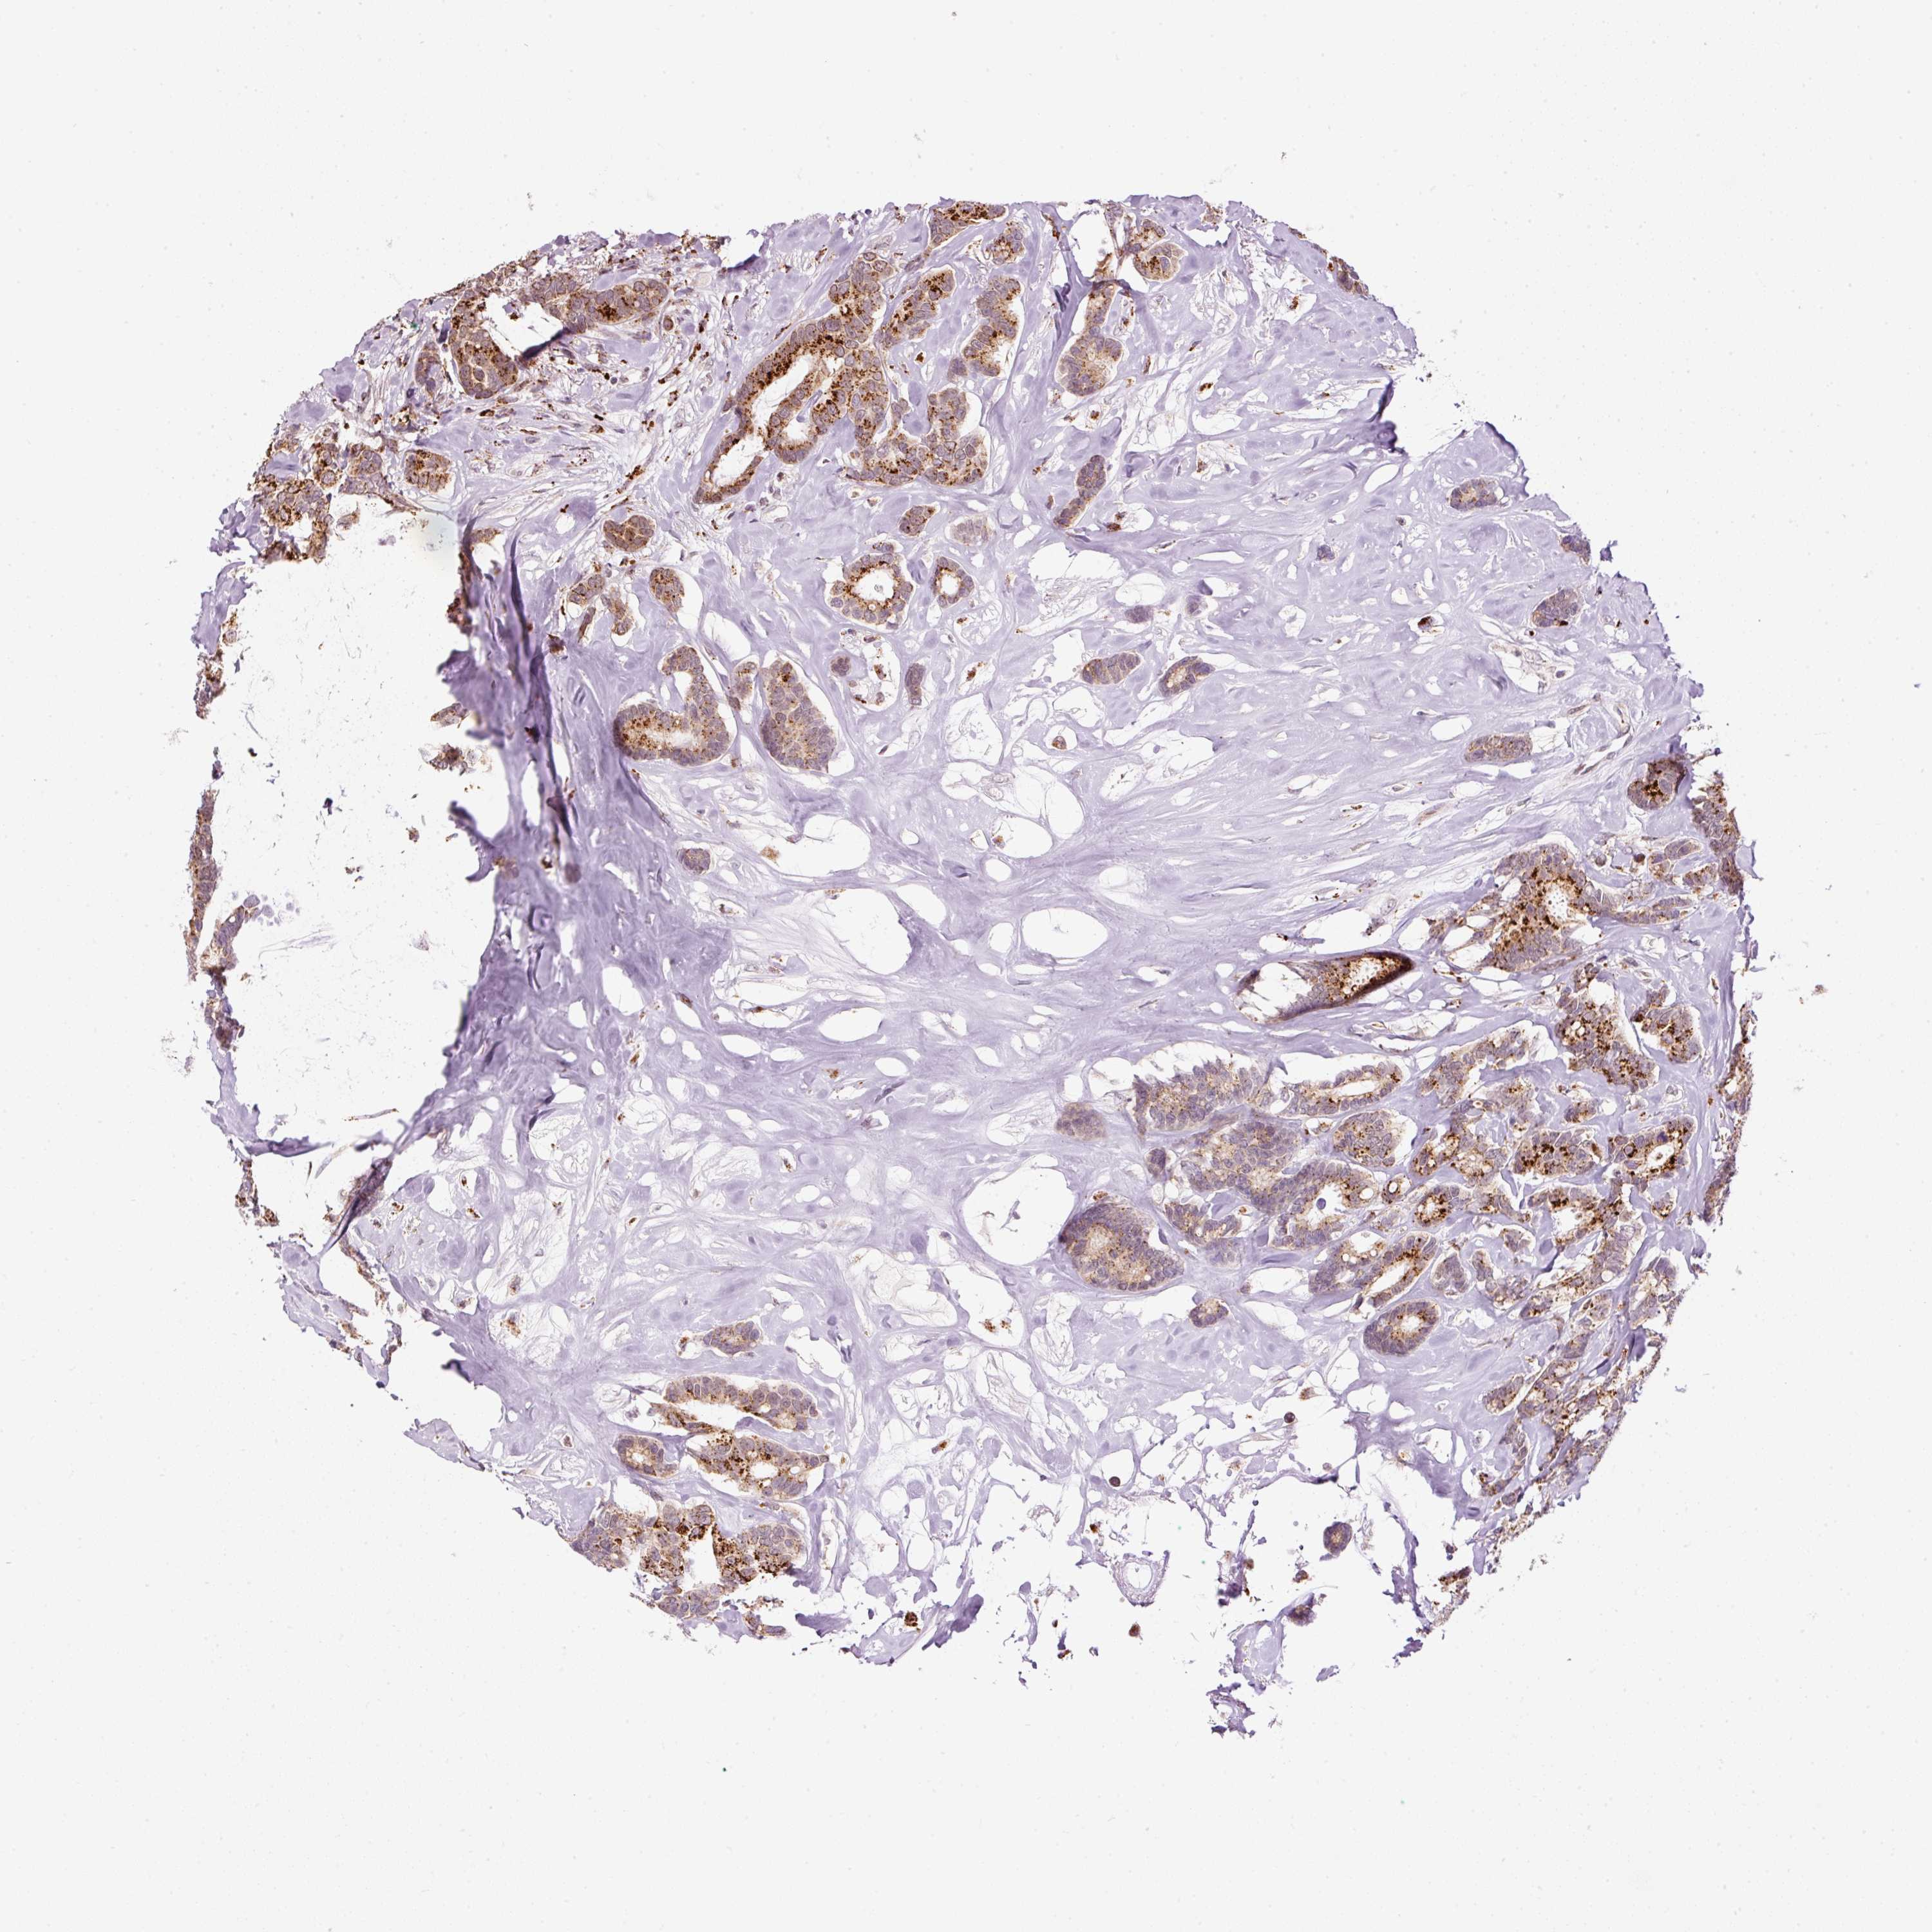

BRCA TCGA BRCA VALIDATION PROTEIN EXPRESSION